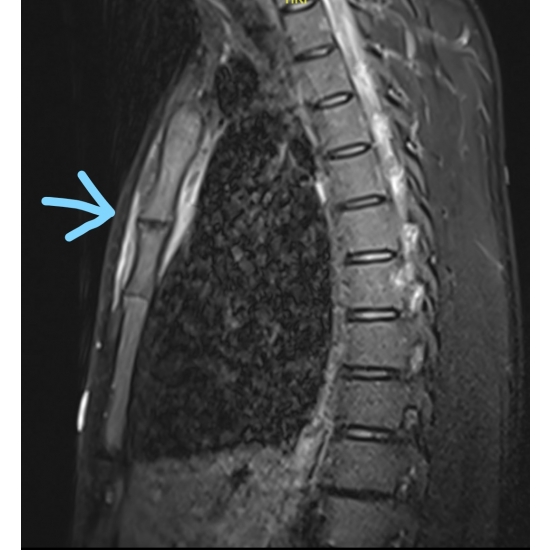

| Row, Row, Row Your Boat, Gently Down The [blood] Stream - Page #3 | |||